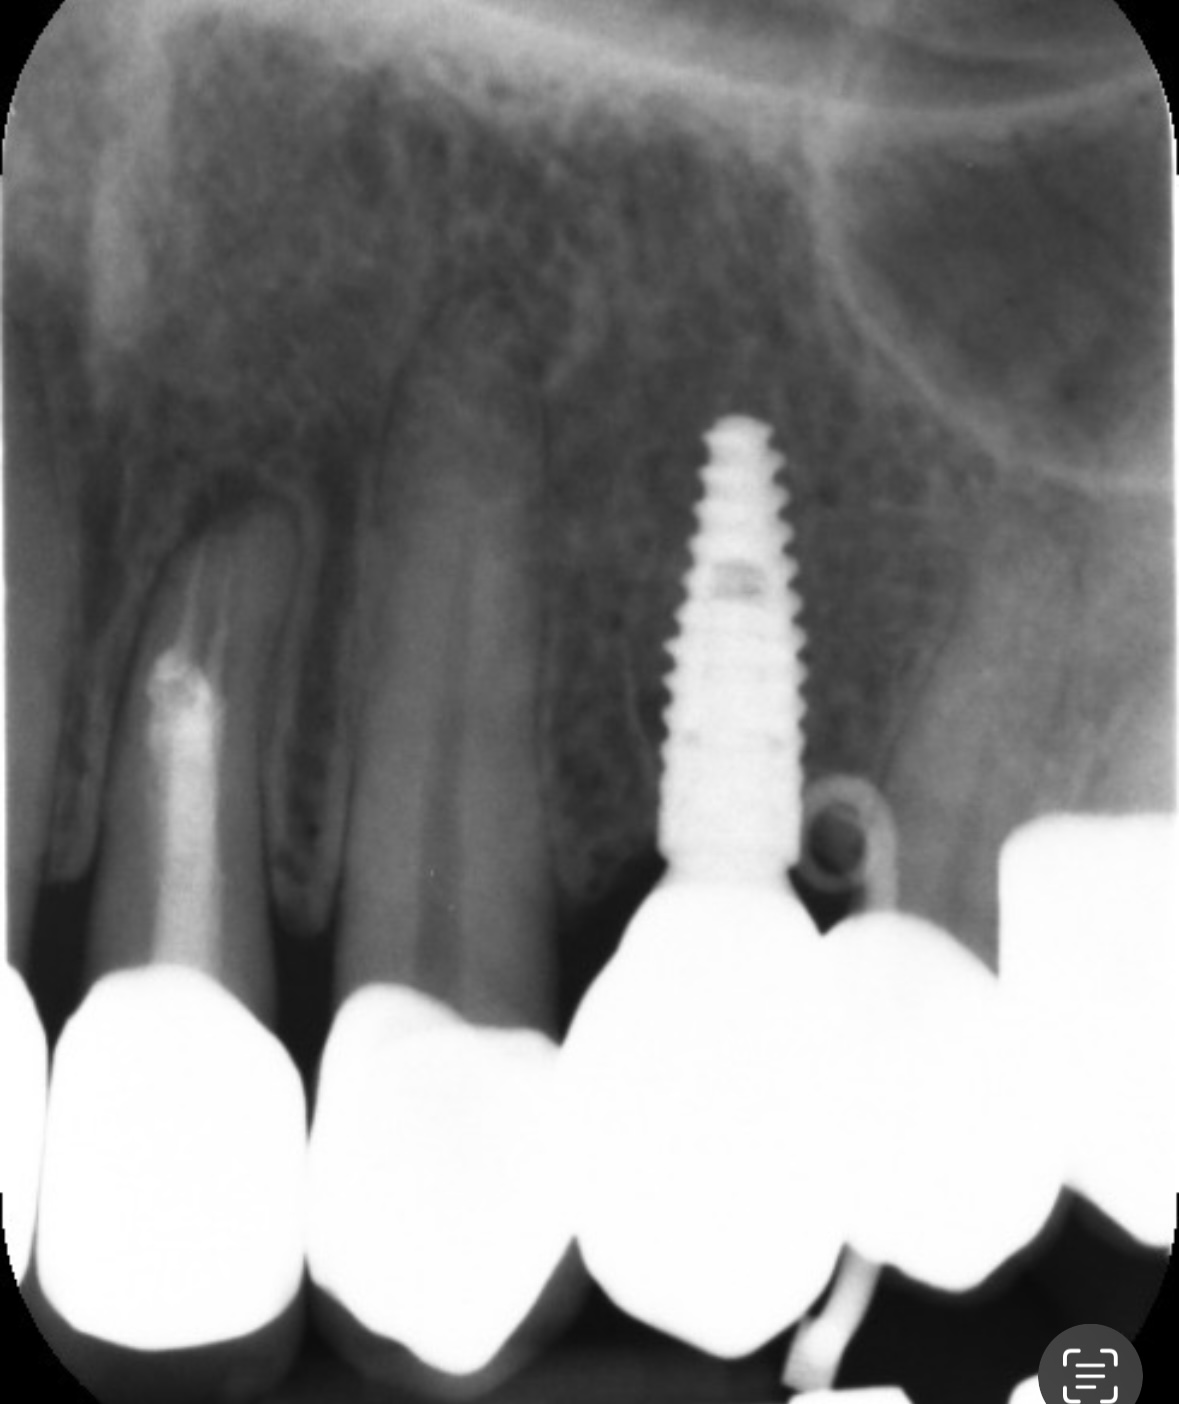

今日また歯医者さんに行き、針のような器具を挿入した状態でレントゲンを撮ってもらいました。その結果、針がインプラントの手前で曲がっていたため、原因はインプラントの歯ではなく、別の歯にあるとのことでした。

先生のお話では、このできものはフィステルであるとのことで、原因としては側切歯の根の部分に炎症があるのでそこの歯からの可能性が高いそうです。とりあえず担当医と相談するように言われましたが、担当医は現在休暇中のため、次回の予約は11月20日になっています。

画像1IMG_0508.jpeg 画像2IMG_0507.jpeg

たまたま根管治療してある側切歯の根尖も問題がありそうだなとわかったのでしょうか。

インプラントもインプラント周囲炎という病気がありますから、専門の先生が来られた際にしっかり診てもらうと良いでしょうね。